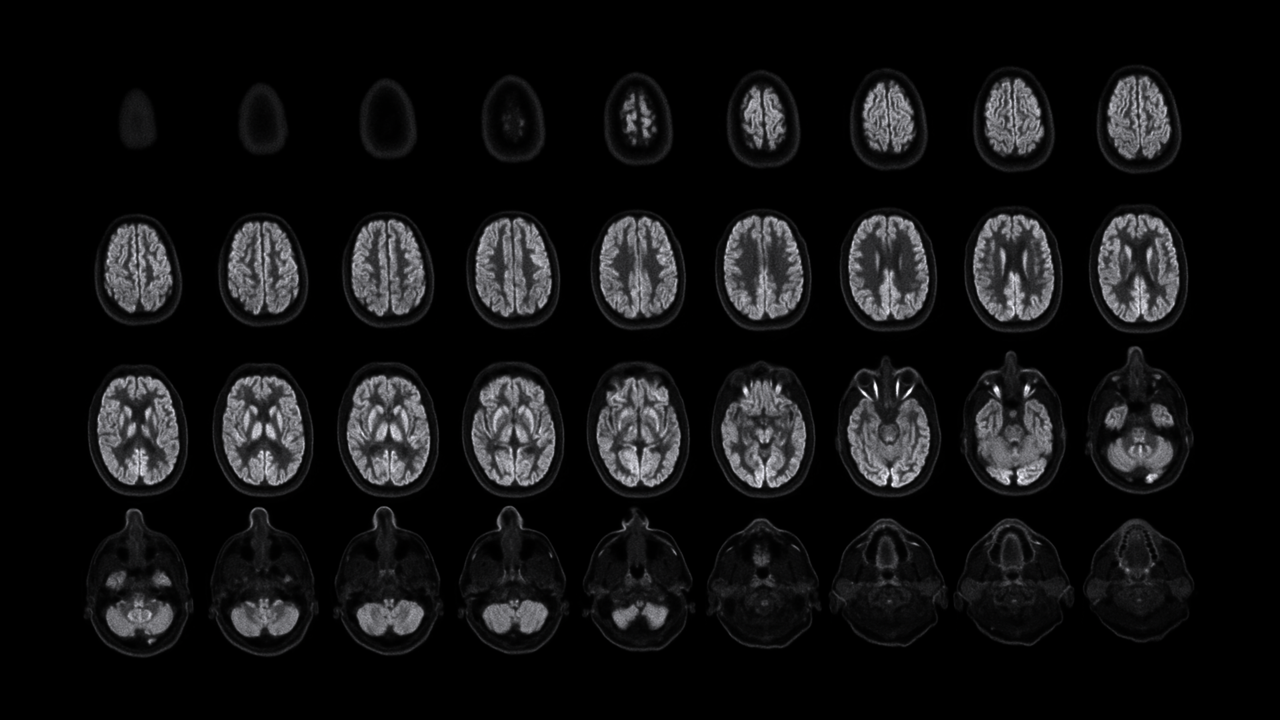

NX正式进驻耶鲁的时间正是2023年的父亲节,Carson教授亲切地称这台下一代高分辨率脑PET系统为“宝贝”,并称这是最好的父亲节礼物。在展示这份”礼物“之前,Carson教授拿出由第一代PET得到的脑部影像。彼时,每一张图像要花至少10分钟才能获取,且由于图像的质量和分辨率极低,几乎很难识别出那是一张脑部图像。 人类对脑部的探索从未停步,对看到其细微末节的需求亦不止。

NeuroExplorer (NX)产出的脑部影像图

NeuroExplorer (NX) 产出到从头顶到肩部区域的完整图像

“从我们目前获取的图像来看,使用NeuroExplorer扫出的图像是世界上最好的,因此我们能够真正做到更好地缩小范围,聚焦更小的信号,观察大脑更为微末的区域,这为我们打开了新的窗口,去‘见所未见’。”Carson教授对NX的诞生和即将围绕其展开的一系列研究满怀期待,“有了NeuroExplorer这样强大的设备,我们步履不停,也正将迎来一个重要的突破,那就是和制药行业的合作。”